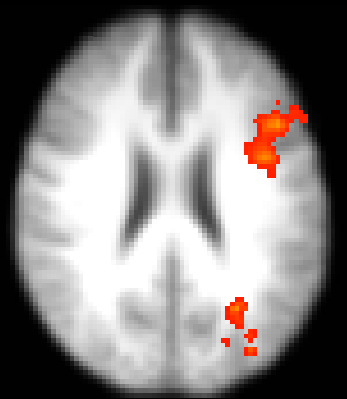

Coupe axiale d’imagerie par résonance magnétique fonctionnelle montrant l’activation unilatérale du cortex préfrontal chez les personnes jeunes lors d’un tâche d’appariement July 8, 2014 • 347 × 399 • Multimédia Like Loading...